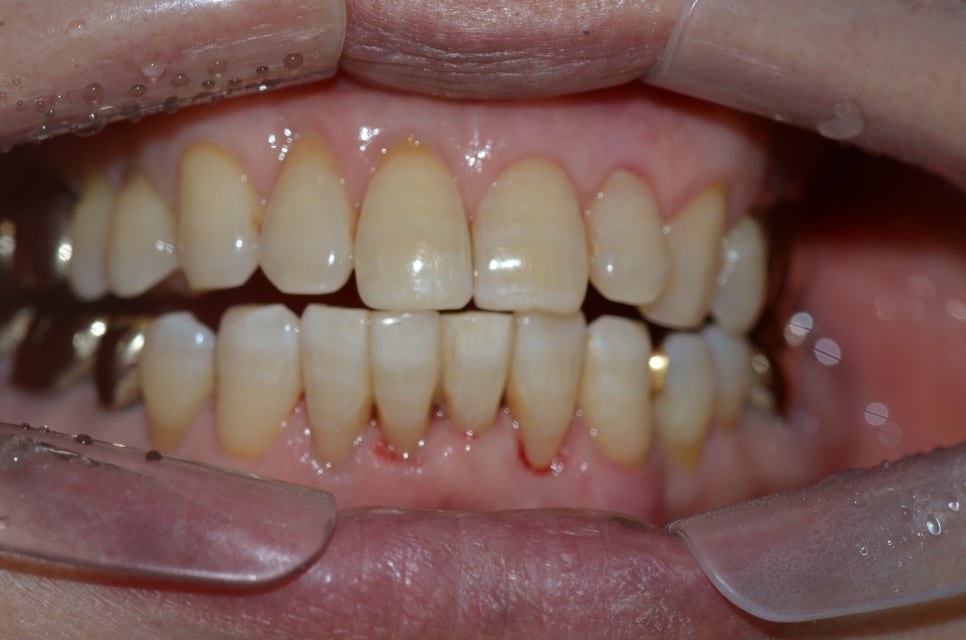

총기간은 6개월 정도 소요되었습니다.

치아가 가지런해졌다며 매우 기뻐하셨습니다.

부분교정은 시간도 적게 걸리고 비용도 상대적으로 많이 저렴하므로 부담갖지 않고 진행할수 있는 것 같습니다.